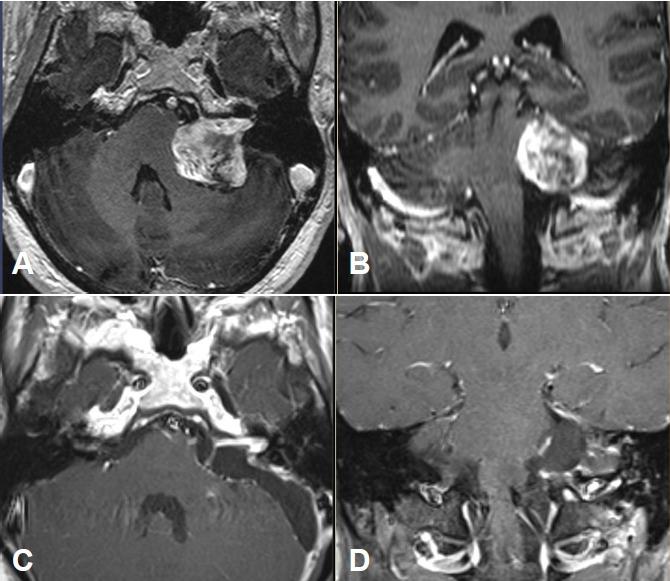

Vestibular schwannomas (VS) expand slowly in the internal auditory canal, in the cerebellopontine angle, inside the cochlear and the labyrinth. Larger tumors can displace and compress the brainstem. With an annual incidence of 1:100,000 vestibular schwannoma represent 6-7% of all intracranial tumors. In the cerebellopontine angle they are by far the most neoplasm with 90% of all lesions located in this region. Magnetic resonance imaging (MRI), audiometry, and vestibular diagnostics are the mainstays of the clinical workup for patients harboring tumors. The first part of this paper delivers an overview of tumor stages, the most common grading scales for facial nerve function and hearing as well as a short introduction to the examination of vestibular function. Upholding or improving quality of life is the central concern in counseling and treating a patient with vestibular schwannoma. Preservation of neuronal function is essential and the management options - watchful waiting, microsurgery and stereotactic radiation - should be custom-tailored to the individual situation of the patient. Continuing interdisciplinary exchange is important to monitor treatment quality and to improve treatment results. Recently, several articles and reviews have been published on the topic of vestibular schwannoma. On the occasion of the 88 annual meeting of the German Society of Oto-Rhino-Laryngology, Head and Neck surgery a special volume of the journal "HNO" will be printed. Hence this presentation has been designed to deviate from the traditional standard which commonly consists of a pure literature review. The current paper was conceptually woven around a series of interdisciplinary cases that outline examples for every stage of the disease that show characteristic results for management options to date. Systematic clinical decision pathways have been deduced from our experience and from results reported in the literature. These pathways are graphically outlined after the case presentations. Important criteria for decision making are size and growth rate of the tumor, hearing of the patient and the probability of total tumor resection with preservation of hearing and facial nerve function, age and comorbidity of the patient, best possible control of vertigo and tinnitus and last but not least the patient's preference and choice. In addition to this, the experience and the results of a given center with each treatment modality will figure in the decision making process. We will discuss findings that are reported in the literature regarding facial nerve function, hearing, vertigo, tinnitus, and headache and reflect on recent studies on their influence on the patient's quality of life. Vertigo plays an essential role in this framework since it is an independent predictor of quality of life and a patient's dependence on social welfare. Pathognomonic bilateral vestibular schwannomas that occur in patients suffering from neurofibromatosis typ-2 (NF2) differ from spontaneous unilateral tumors in their biologic behavior. Treatment of neurofibromatosis type-2 patients requires a multidisciplinary team, especially because of the multitude of separate intracranial and spinal lesions. Off-label chemotherapy with Bevacizumab can stabilize tumor size of vestibular schwannomas and even improve hearing over longer periods of time. Hearing rehabilitation in NF2 patients can be achieved with cochlear and auditory brainstem implants.

前庭神经鞘瘤(VS)在内耳道、桥小脑角、耳蜗和迷路内缓慢生长。较大的肿瘤可移位并压迫脑干。前庭神经鞘瘤的年发病率为1:100,000,占所有颅内肿瘤的6 - 7%。在桥小脑角,它们是迄今为止最常见的肿瘤,90%的病变位于该区域。磁共振成像(MRI)、听力测定和前庭诊断是患有肿瘤患者临床检查的主要手段。本文的第一部分概述了肿瘤分期、面神经功能和听力最常用的分级量表,并简要介绍了前庭功能检查。维护或改善生活质量是咨询和治疗前庭神经鞘瘤患者的核心关注点。保留神经功能至关重要,管理选择——观察等待、显微手术和立体定向放射治疗——应根据患者的个体情况量身定制。持续的跨学科交流对于监测治疗质量和改善治疗结果很重要。最近,关于前庭神经鞘瘤的主题发表了几篇文章和综述。在德国耳鼻咽喉头颈外科学会第88届年会上,将出版一期《HNO》杂志特刊。因此,本报告旨在偏离通常由纯文献综述组成的传统标准。本文围绕一系列跨学科病例进行概念性构建,这些病例概述了疾病各阶段的示例,展示了迄今为止管理选择的特征性结果。系统的临床决策路径已根据我们的经验和文献报道的结果推导得出。这些路径在病例报告后以图表形式概述。决策的重要标准包括肿瘤的大小和生长速度、患者的听力以及在保留听力和面神经功能的情况下肿瘤全切的可能性、患者的年龄和合并症、尽可能最佳地控制眩晕和耳鸣,最后但同样重要的是患者的偏好和选择。除此之外,特定中心每种治疗方式的经验和结果也将纳入决策过程。我们将讨论文献中报道的关于面神经功能、听力、眩晕、耳鸣和头痛的研究结果,并思考近期关于它们对患者生活质量影响的研究。眩晕在这个框架中起着至关重要的作用,因为它是生活质量的独立预测因素以及患者对社会福利依赖程度的指标。患有2型神经纤维瘤病(NF2)的患者出现的典型双侧前庭神经鞘瘤在生物学行为上与自发性单侧肿瘤不同。治疗NF2患者需要一个多学科团队,特别是因为存在众多单独的颅内和脊髓病变。使用贝伐单抗进行的非标签化疗可以稳定前庭神经鞘瘤的肿瘤大小,甚至在较长时间内改善听力。NF2患者的听力康复可以通过人工耳蜗和听觉脑干植入来实现。